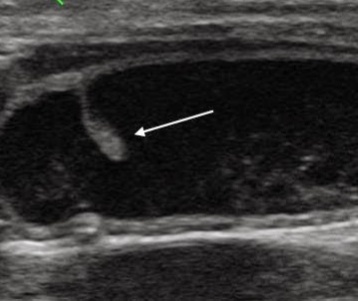

Стрелкой указан полип